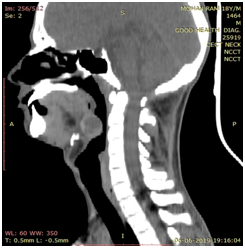

We present a case of a 18 years old male who presented to our outpatient clinic with chief complaints of persistent cough and foreign body sensation since one month. He was completely asymptomatic before that. There was no history of weight loss, prolonged fever, sputum production and sore throat. There was no history suggestive of hypothyroidism. On examination, there was a small soft cystic midline swelling of size 4x3 cm at the base of tongue extending to left lateral side (Figure 1). It was not bleeding on touch. Neck examination revealed absence of thyroid gland on palpation. There were no palpable neck nodes. Indirect laryngoscopy showed bilateral vocal cord mobility with normal endolarynx. Ultrasound neck showed absence of thyroid gland in normal anatomical location. Thyroid function test revealed T3- 1.31 ng/ml, T4-8.7ug/dl, TSH-24.18uiu/ml. After getting endocrinology opinion, patient was started on 50 microgram of L-thyroxine. Further evaluation in the form of contrast enhanced computed tomography scan neck revealed cystic swelling of 3x2 cm size with peripheral rim of enhancement suggestive of thyroid tissue at the base of tongue and absence of thyroid gland in normal anatomical location (Figure 2). Technetium 99m scan suggested increased isotope uptake at base of tongue and no uptake at the normal thyroid location.

Figure 2 CECT scan showing a well-defined cystic swelling (indicated by arrow) of 3x2cm size with peripheral rim of enhancement at base of tongue. (Axial and Sagittal view).